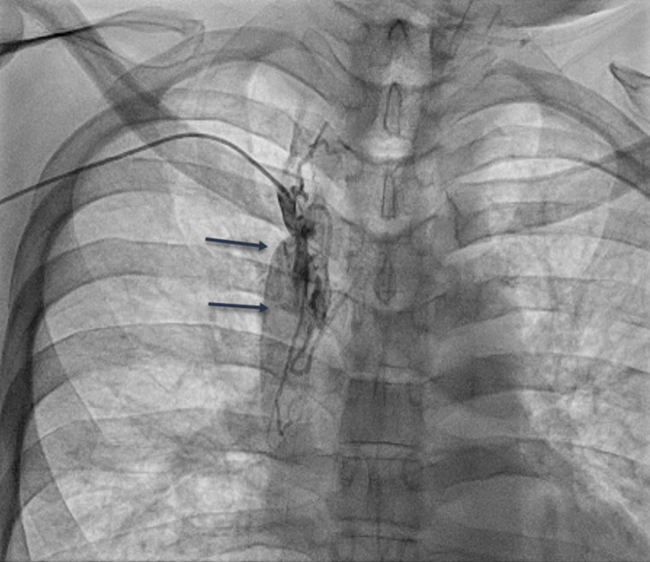

RHC procedure. Arm venous access was obtained with ultrasound guidance in all cases. After successful ‘radial’ sheath insertion, a 5-French (Fr) or 6-Fr balloon flotation right heart catheter was advanced (either by itself or over a 0.014-inch coronary guidewire based on operator preference) through the sheath and then into the pulmonary artery (PA). If resistance to catheter passage was encountered, a venogram (Figures 1A, 2A, and 3A) was performed using diluted contrast (50% saline) to determine the venous anatomy, the location, and the extent of stenosis, and to guide further wire/catheter advancement. In some cases, using different guidewires or catheters (eg, downsizing a 6 Fr to a 5 Fr) allowed RHC success. When a 0.014-inch wire was advanced into the superior vena cava (SVC) and the passage of a balloon-tip right heart catheter over the wire was unsuccessful due to a stenosis and/or pacemaker/ICD wires, a coronary balloon or 0.014-inch compatible peripheral balloon was then advanced over the wire and dilatation of the stenosis was performed (Figures 1B, 2B, and 3B). In some cases, a single balloon dilatation allowed passage of the RHC catheter. In others, a progressive increase in balloon diameters was needed. At the end of the procedure, the venous sheath was withdrawn, and manual compression was applied to the puncture site until hemostasis was attained.

We were able to pass a guidewire through all stenoses. A coronary or peripheral balloon catheter was then passed over the guidewire, and dilatation was performed (Figures 1B, 2B, and 3B). Coronary angioplasty balloons were utilized in 8 (44.4%), peripheral balloons in 7 (38.9%), and both peripheral and coronary balloons in 3 patients (16.7%). The balloons used were predominantly non-compliant (83.3%). Eleven patients (61.1%) required only a single balloon for successful venoplasty, while 7 patients (38.9%) had at least 2 balloons used, upsizing from the previously used balloon. The balloons' median diameter and length were 4 mm (range, 3-4 mm) and 60 mm (range, 20-200 mm), respectively. The median highest inflation pressure used was 14 atm (range, 8-18). After SVS dilatation, we performed successful RHC in 100% of the cases with a catheter passed into the PA. The average length of the procedure for successful RHC was 35.2 ± 15.5 minutes. There were no complications at the end of the procedure in any of our patients.